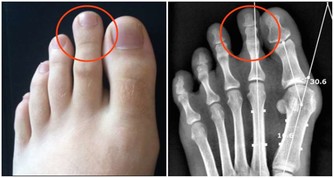

多動腳趾養脾胃

脾胃不好的病人多動腳趾,相當於按摩脾胃二經。上班時,可以邊工作邊用腳趾抓地、抓鞋底,每次抓5分鐘。或者在洗腳盆裡放一些橢圓形、大小適中的鵝卵石,邊泡腳邊用腳趾抓石頭。